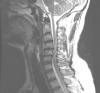

Varón de 54 años, fumador, con consumo abusivo de alcohol y con síndrome antifosfolípido primario anticoagulado. Fue trasladado tras ser encontrado en el suelo donde había permanecido 5 horas por imposibilidad para la movilización. No...

Neurología: Patología de raquisEtiología: TraumaDiagnóstico final: Mielopatía post-traumática tras hiperextensión cervicalNivel de certeza: